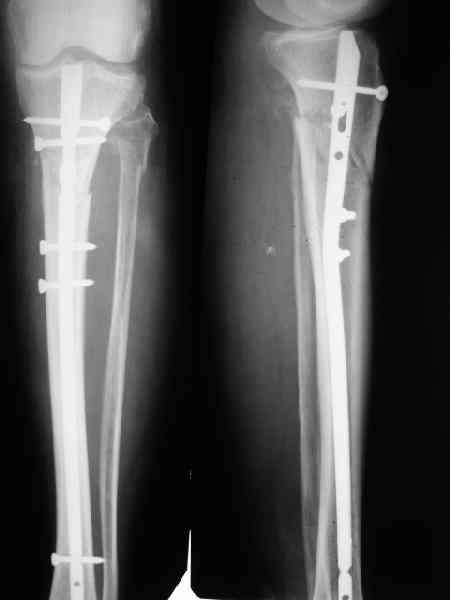

В приложении как раз видна эволюция использововшихся у нас большеберцовых гвоздей. Первый - дизайн как у UTN, второй - разнесены 45 градусные отверстия (зачем их вообще изначально так нелепо на одном уровне сделалм???), третий - убрано сиавшее лишним статическое отверстие, Herzog's bend перемещен более проксимально.